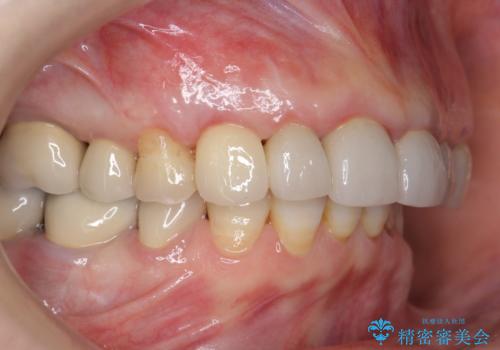

クラウン下に再発した深い虫歯 インプラントによる機能回復

- 45万円(ストローマンインプラント・骨造成・チタンカスタムアバットメント・ジルコニアクラウン)費用は治療当時の料金となります

前歯のインプラントを仕上げるには骨や歯ぐきの条件を整えることが肝要です。